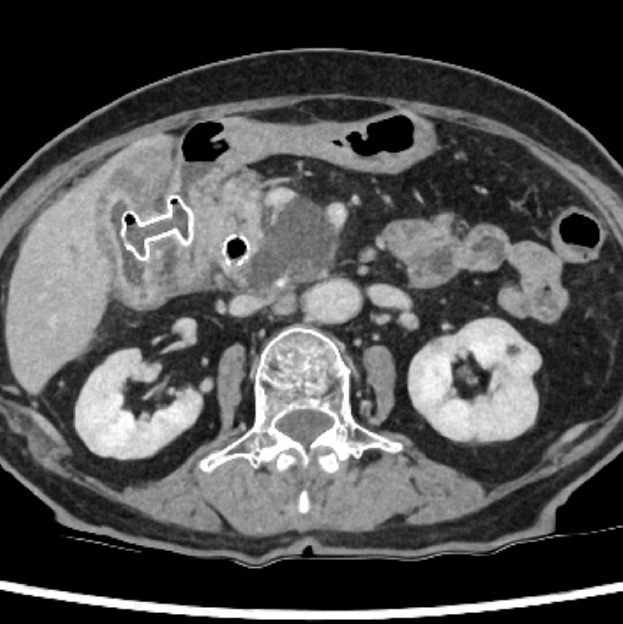

重症急性膵炎後のWONに対するEUS下膿瘍ドレナージ

肝門部胆管癌に対するEUS下胆道ドレナージ

急性胆嚢炎に対するEUS下胆嚢ドレナージ(LAMS留置)